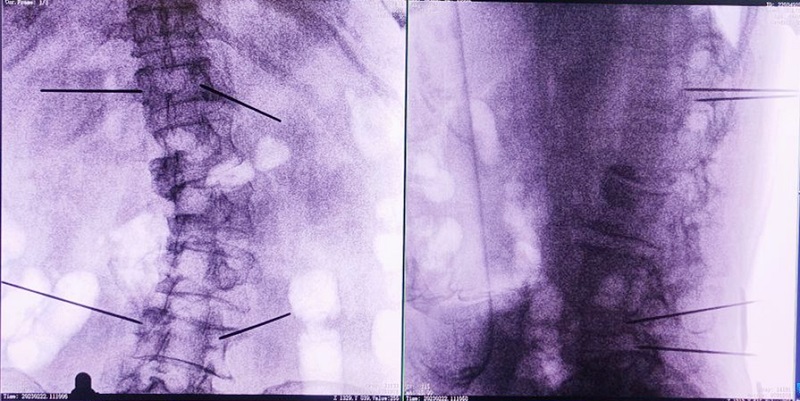

(3)根據(jù)設(shè)定好的的位置和入針方向,植入引導(dǎo)針;

(4)所有引導(dǎo)針植入完畢后,沿引導(dǎo)針方向進(jìn)行椎弓根及椎體置管,建立通道;

(5)沿通道注入骨水泥,恢復(fù)椎體高度,并觀察其擴(kuò)散情況,達(dá)到滿意效果后,停止注入骨水泥。